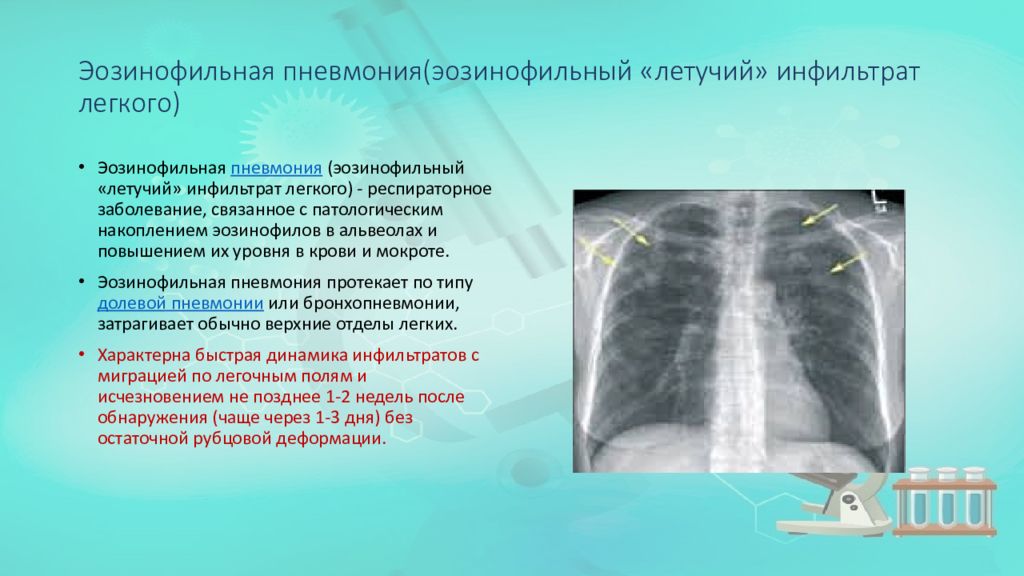

Иллюстрации по теме очагового и инфильтративного туберкулеза